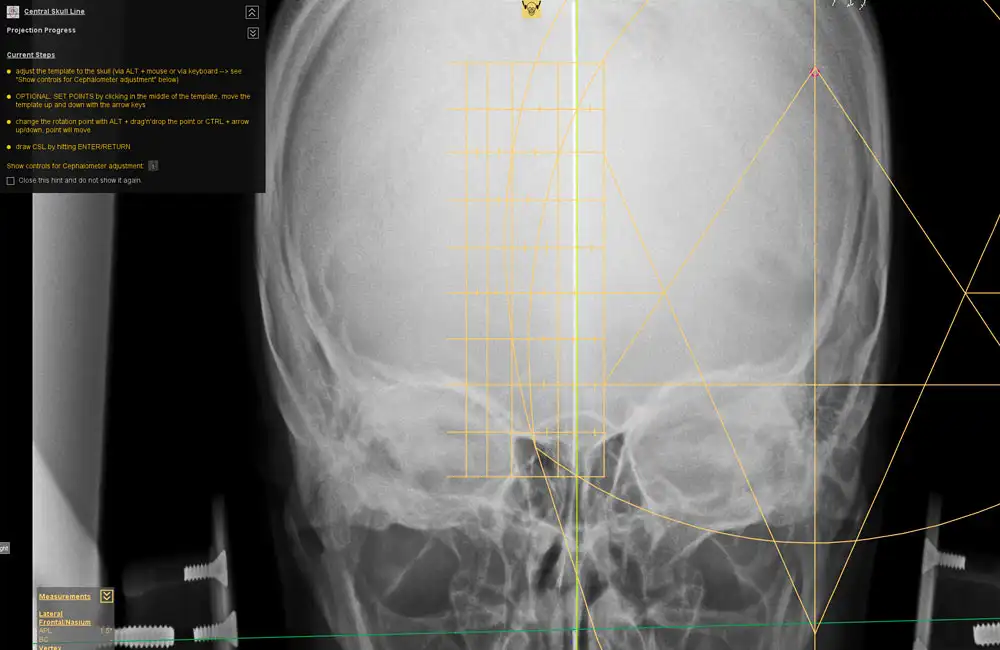

The dicomPACS® Upper Cervical (NUCCA) Chiropractic Tool Set was developed in close collaboration with leading NUCCA experts from the United States and Canada. It provides everything required for fast and highly precise diagnostics in the upper cervical spine. Specialized NUCCA templates such as the cephalometer, grid, circumscale, and relatoscope support a familiar workflow while ensuring maximum accuracy.

Using manual point marking, the software automatically generates midlines, reference points, curves, and angles, significantly improving the efficiency of diagnosis and treatment planning. The NUCCA Tool Set is complemented by all essential standard chiropractic tools, including distance and angle measurements, Cobb angles, and marker points—delivering a comprehensive, professional NUCCA analysis within a single, integrated solution.

Cephalometer, grid, circumscale, and relatoscope for precise analysis with a familiar workflow.

Automatic generation of midlines, reference points, curves, and angles based on manual point marking.